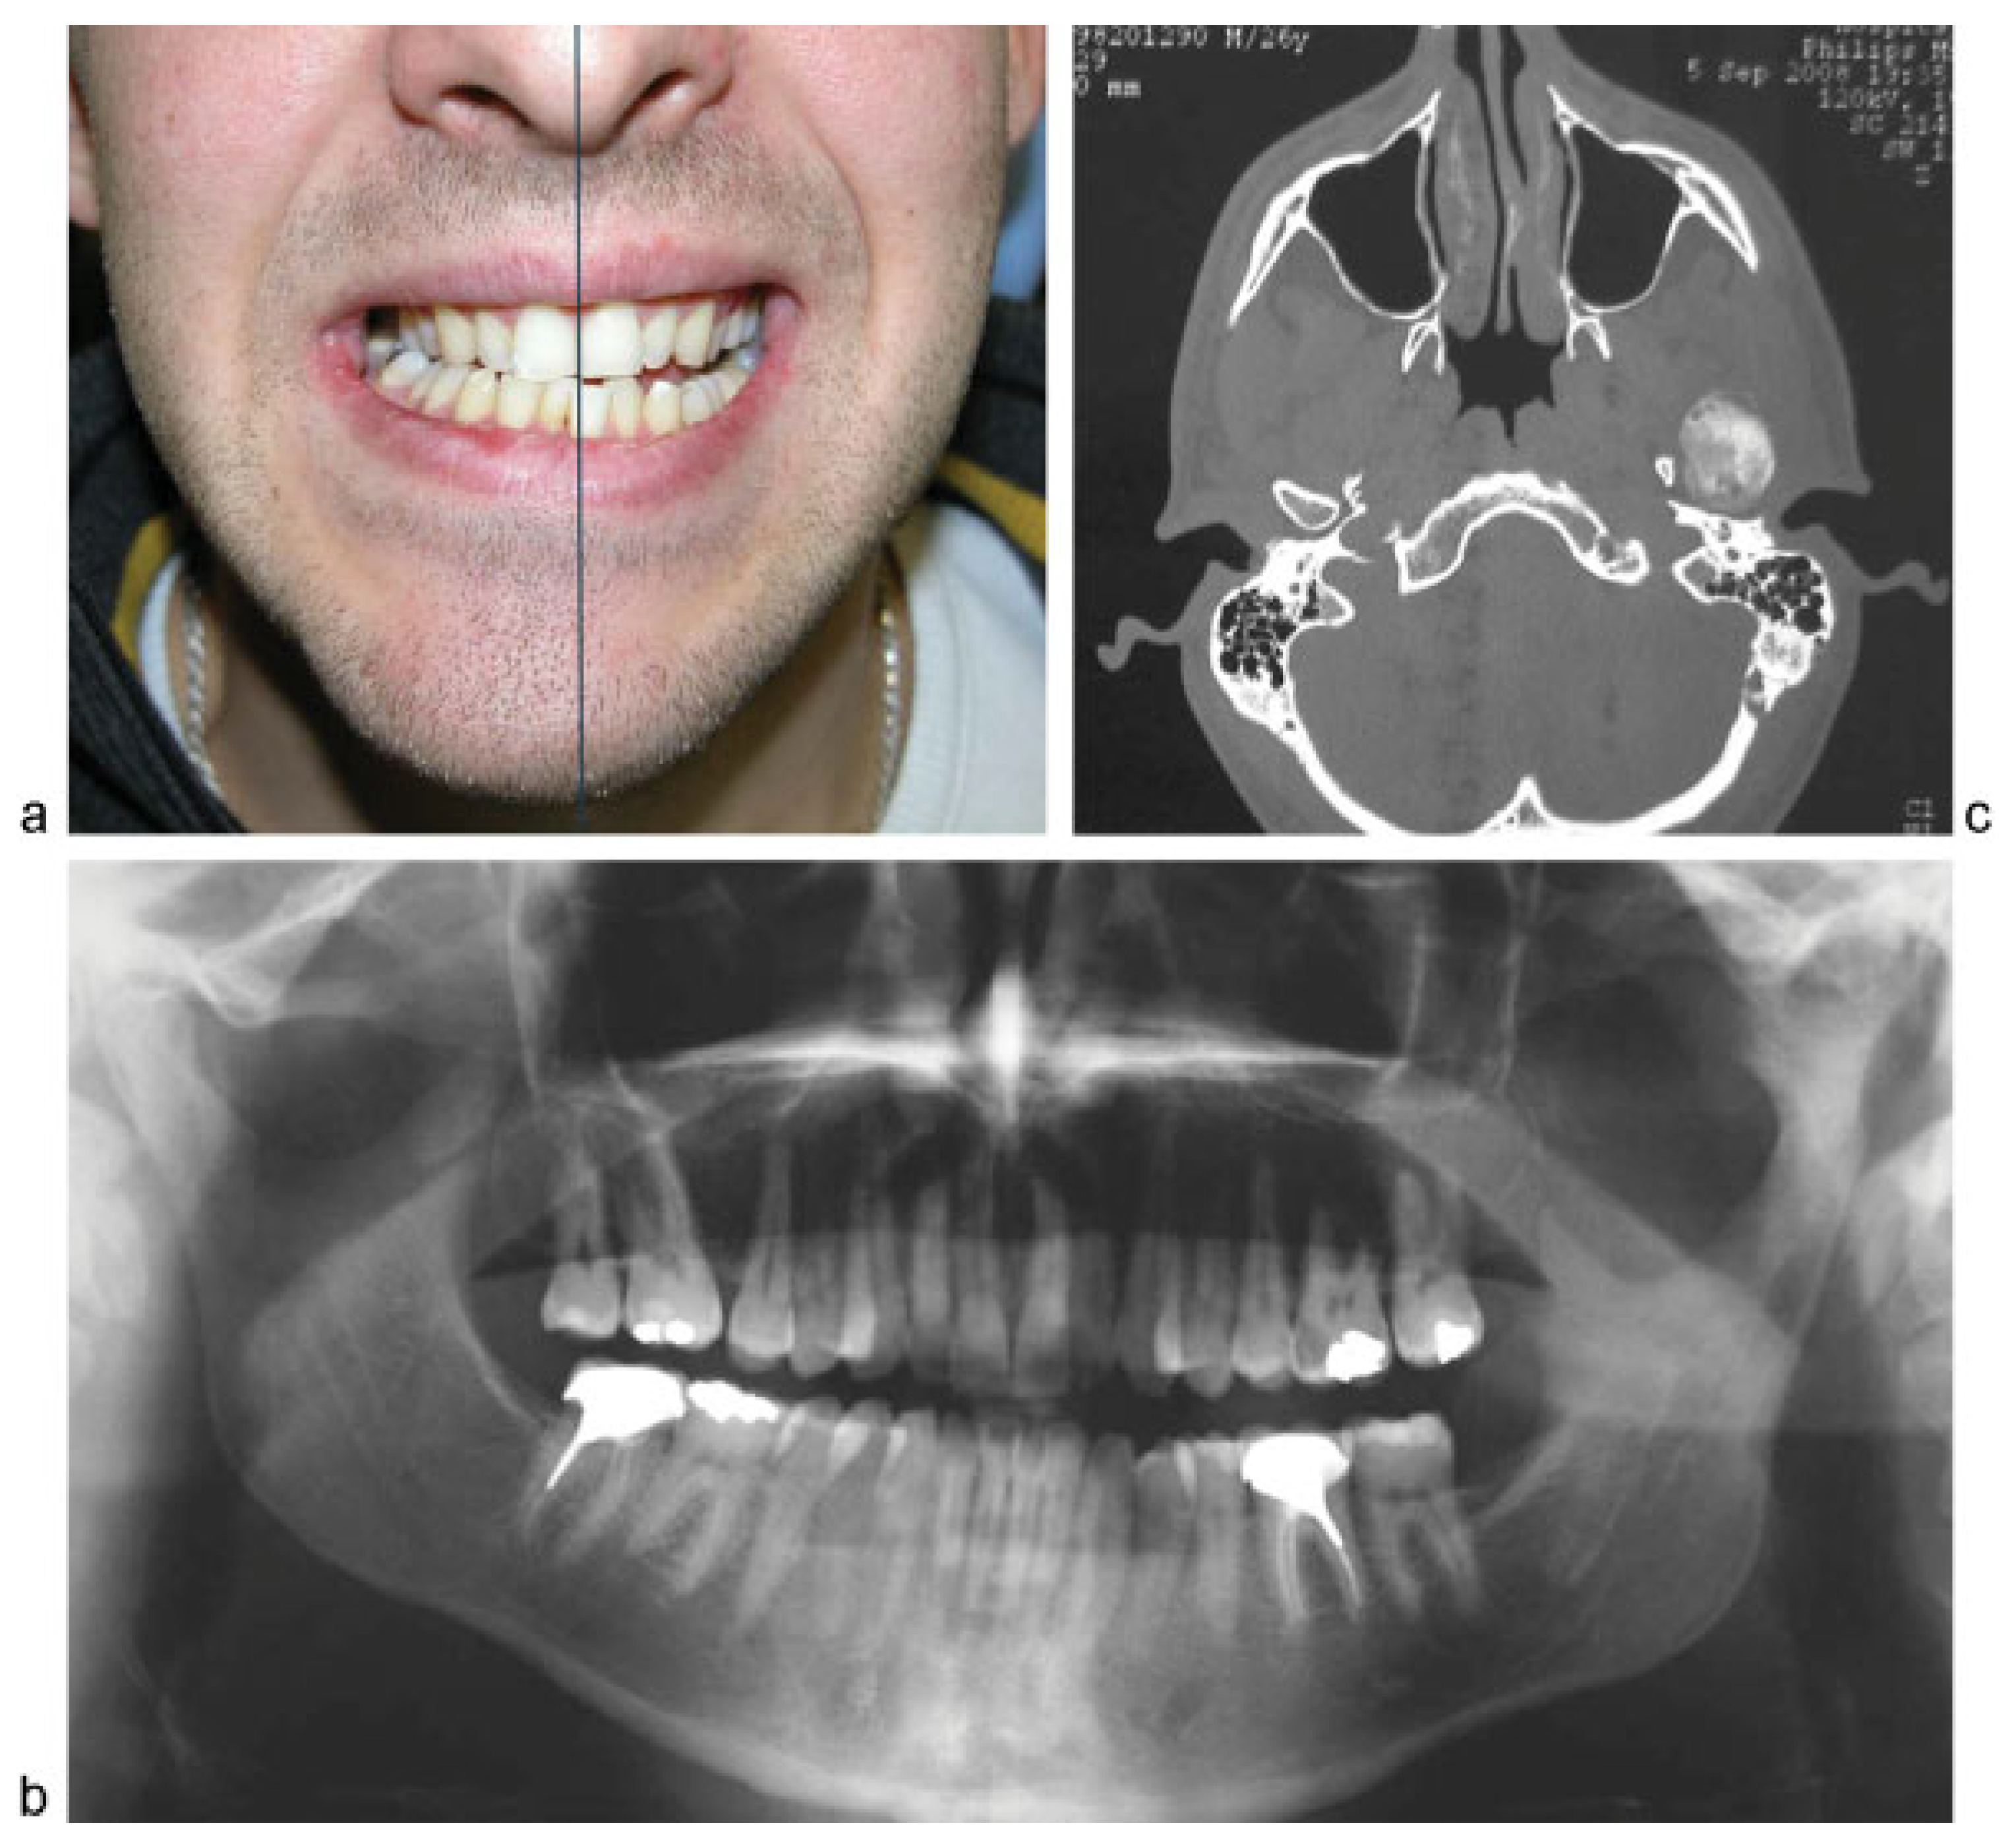

Condylar Osteochondroma Treated with Total Condylectomy and Preservation of the Articular Disc: A Case Report

Case Report